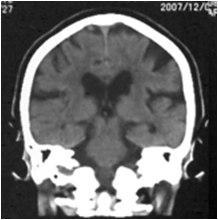

特発生正常圧水頭症のCT画像

特発生正常圧水頭症の特徴的CT所見(通常は脳を水平に撮影しますが、冠状に撮影した画像のほうがより特徴を捉えることができます)

- 脳の上のほうの隙間が狭い

- 前頭葉と側頭葉の隙間が大きく開く

- 局所的に大きな脳の隙間がある

- V字型になる(正常では直線に近い)